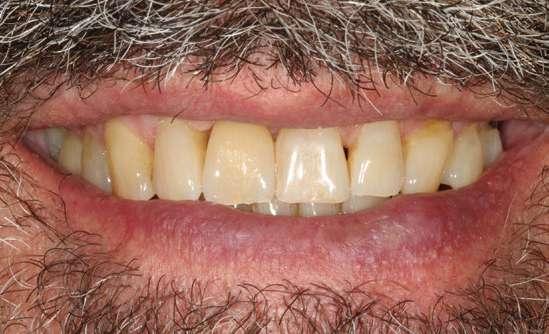

Presentamos el caso de un paciente masculino de 61 años de edad, bruxista, con evidentes desgastes en toda la dentición y cracks de esmalte que pueden observarse en las fotografías iniciales de la primera visita (figuras 1 y 2). En las fotografías

Figuras 1 y 2. Imágenes intraorales de la primera visita donde se hacen evidentes diferentes desgastes en los dientes anteriores y a mayor detalle crakcs en el esmalte, así como lesiones por abfracción en los cuellos de los dientes de los premolares y caninos superiores.